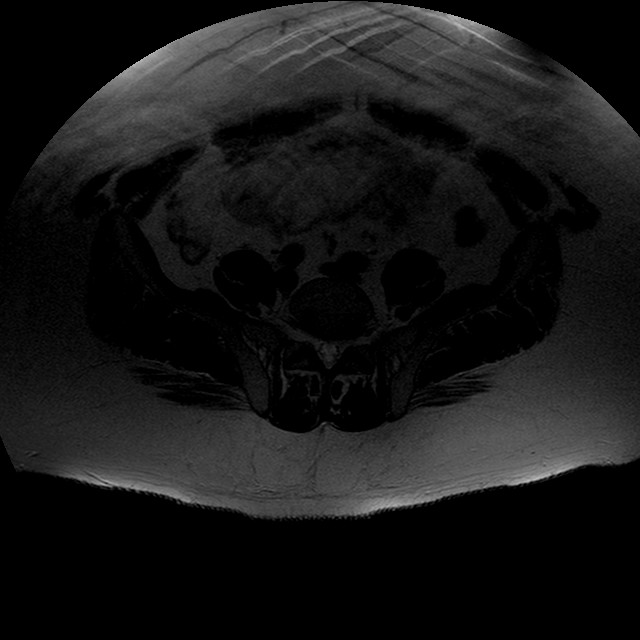

Esami: RMN BACINO

T2w TSE

Evidenti e simmetriche alterazioni osteofitosiche in regione coxo femorale con riduzione delle rime articolari. Degenerazione completa del cercine glenoideo. Non attuali segni di versamento articolare. Non segni di edema osseo che escludono attuale algodistrofia od osteonecrosi. Lieve e simmetrica riduzione del trofismo della muscolatura glutea.